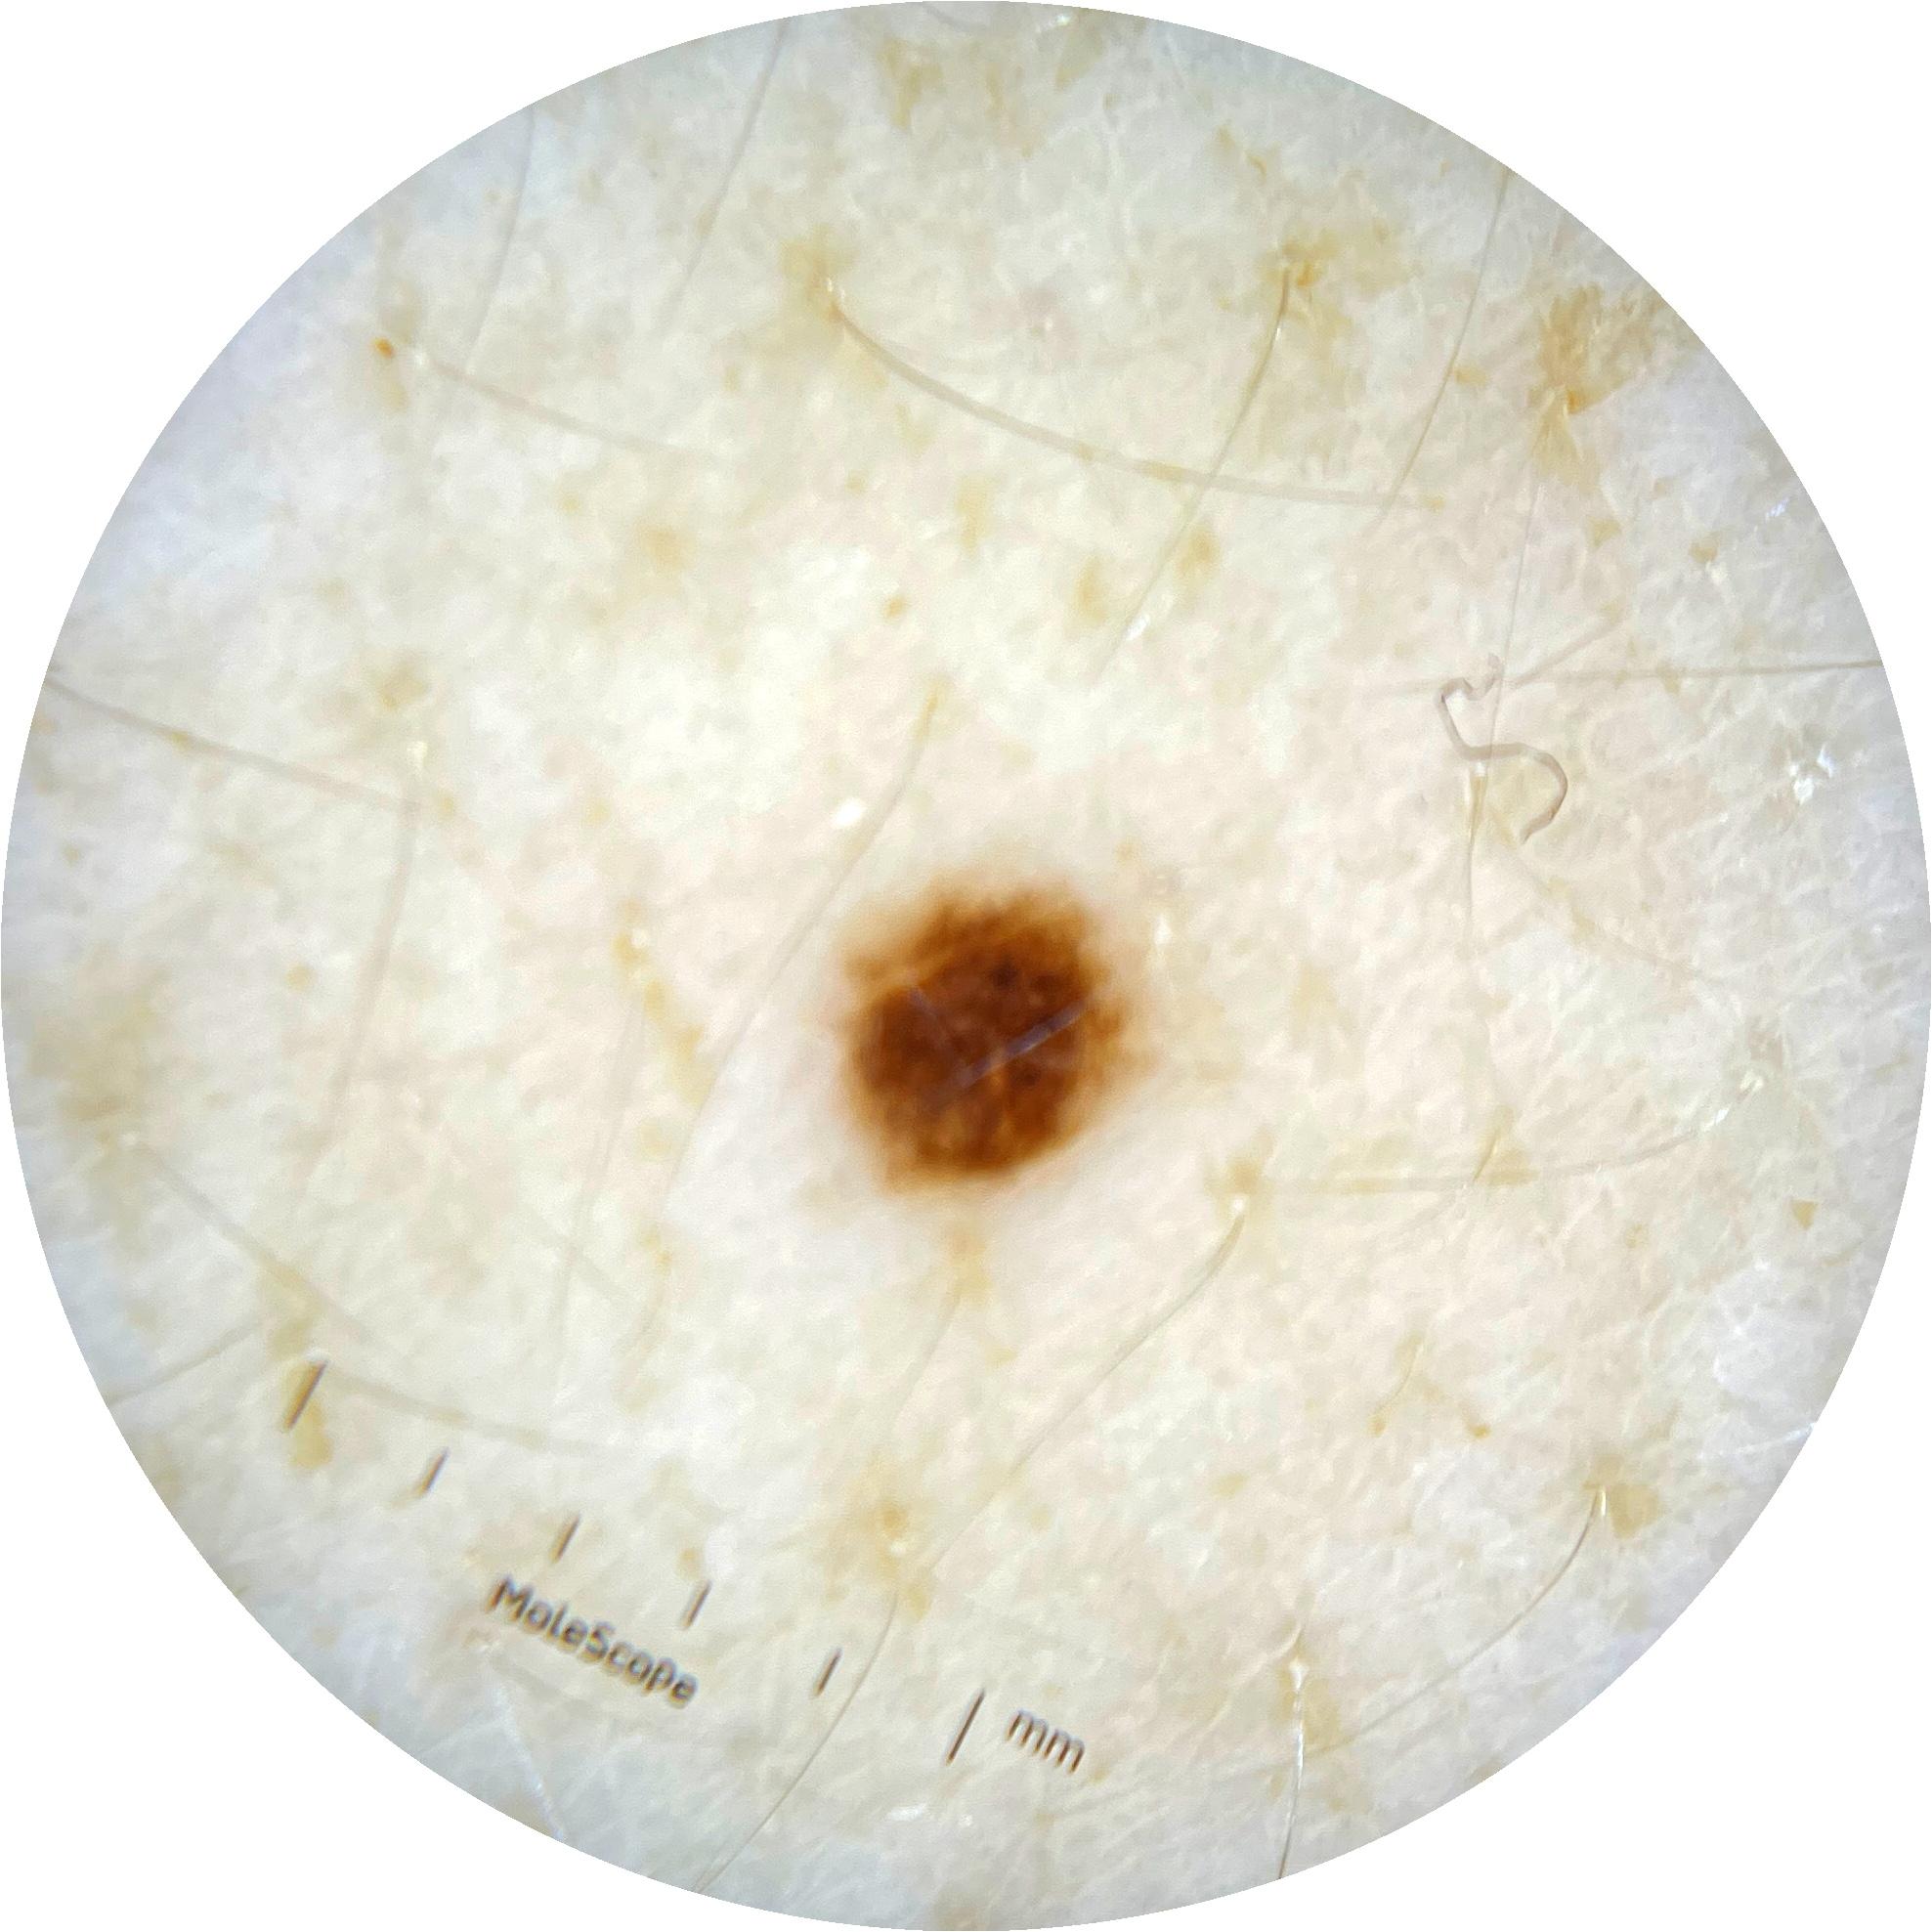

ISIC_0301375

1986 x 1986

Clinical

Field Value

acquisition_day 331

age_approx 35

anatom_site_1 Trunk

anatom_site_2 Anterior trunk

anatom_site_general anterior torso

diagnosis_1 Benign

diagnosis_confirm_type single image expert consensus

image_type dermoscopic